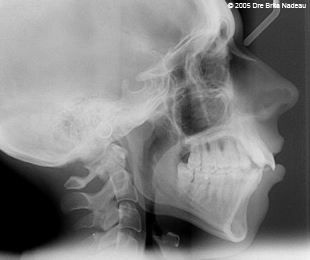

- Photos & radiographies